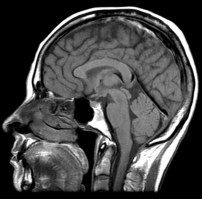

There are two kinds of neuroimaging (brain mapping): structural and functional. A structural neuroimage looks at the parts of the brain to see if they are there and intact. CT scans and MRI look at the parts, they are structural neuroimaging techniques.

Here’s an example of a structural neuroimage from a standard MRI. This allows you to see if the parts are there, but not if they are working right. It’s like looking at the engine of a car. It may look fine but unless you try to start it you don’t know if it runs. It is an interesting fact that the MRI of a live brain is indistinguishable from that a dead one.